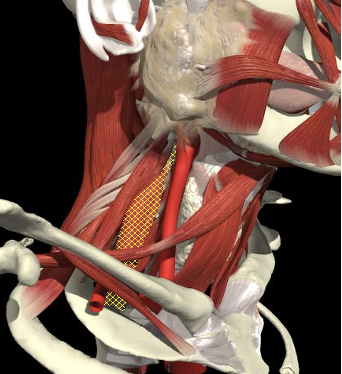

Structures to Avoid

Brachial Plexus

The BP lies inferior to a line from the posterior margin of the sternomastoid at the level of the cricoid cartilage to the midpoint of the clavicle

The BP lies inferior to a line from the posterior margin of the sternomastoid at the level of the cricoid cartilage to the midpoint of the clavicle. Scalenus medius is behind and above line.

Interscalene Groove & Brachial Plexus

Interscalene groove